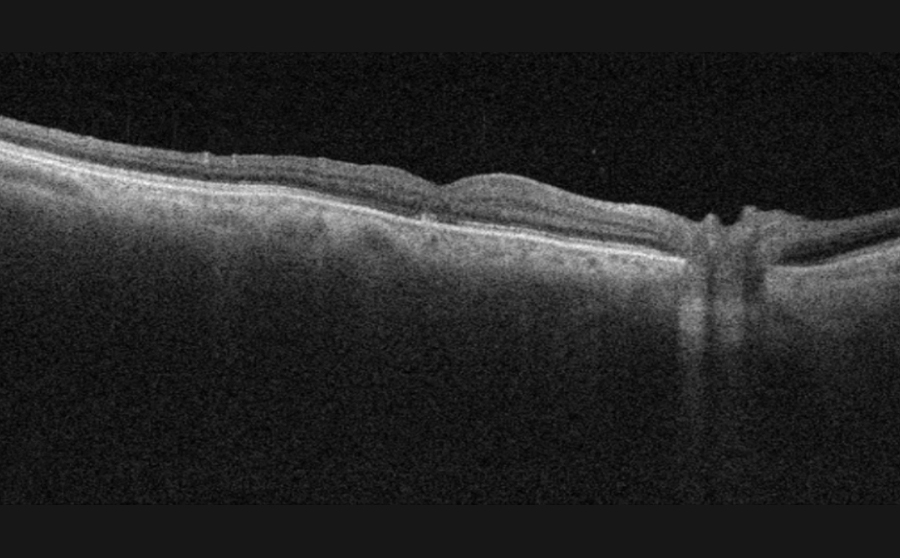

- OCT (optical coherence tomography) is a non-invasive scan of the retina which confirms the diagnosis. OCT takes cross-sectional images of the retinal layers and helps in ruling out other similar-looking diseases of the eye. It also helps to pick up any early changes in the fellow eye.

Gass first described his clinical observations on the evolution of a macular hole (MH) as follows (2)

- Stage 1 (impending MH): Loss of foveal depression.

- Stage 1A: Foveolar detachment with loss of contour and a lipofuscin-colored spot.

- Stage 1B: Foveal detachment with a lipofuscin-colored ring.

- Stage 2: Full-thickness break < 400 µm. in size in the fovea.

- Stage 3: Full-thickness foveal defect ≥ 400 µm; in size. A grayish macular rim often denotes a cuff of subretinal fluid. Usually, PVD is started in this stage with or without an operculum.

- Stage 4: Stage 3 MH with a complete posterior vitreous detachment (PVD) and a Weiss ring.